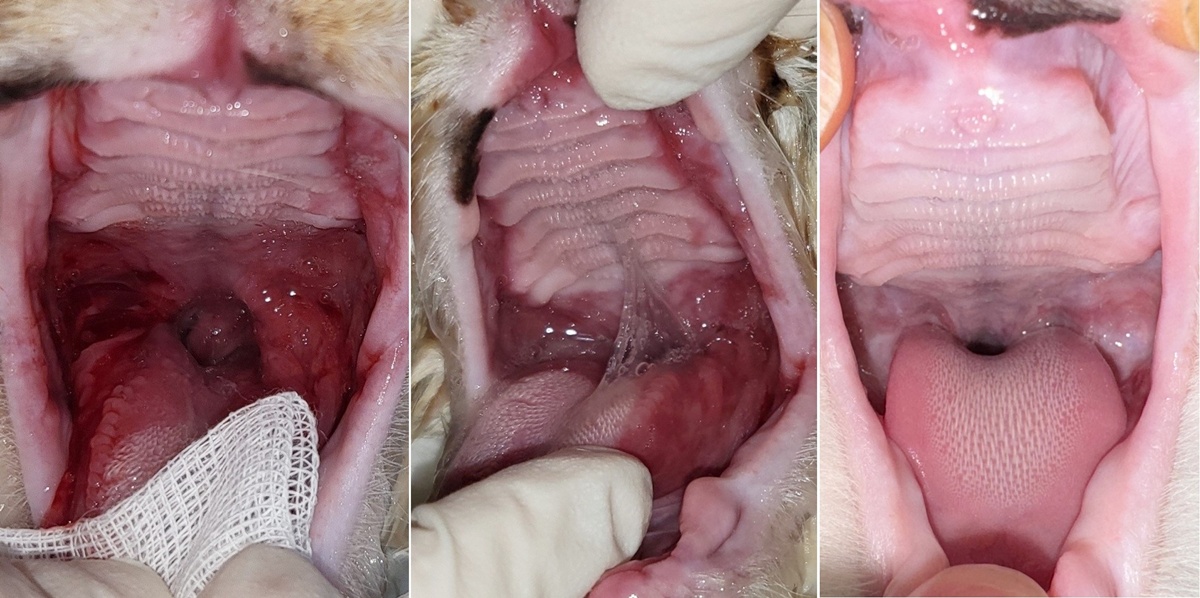

구내염으로 다른 병원에서 전발치를 했지만, 구내염이 해소되지 않았던 케이스(위 사진)가 기억납니다.

내복약을 중단하지 못하고 투약 중에 저희 병원에서 애니씰C 덴탈콜라겐을 3회 적용했고, 지금은 애프터 사진(사진 우측 첫 번째)처럼 구내염이 해소된 케이스가 있습니다. 지금은 내복약도 중단한 상태로, 간혹 불편감을 호소할 때만 간헐적으로 내복약을 짧게 처방하는 정도로 유지하며 관리 중입니다.